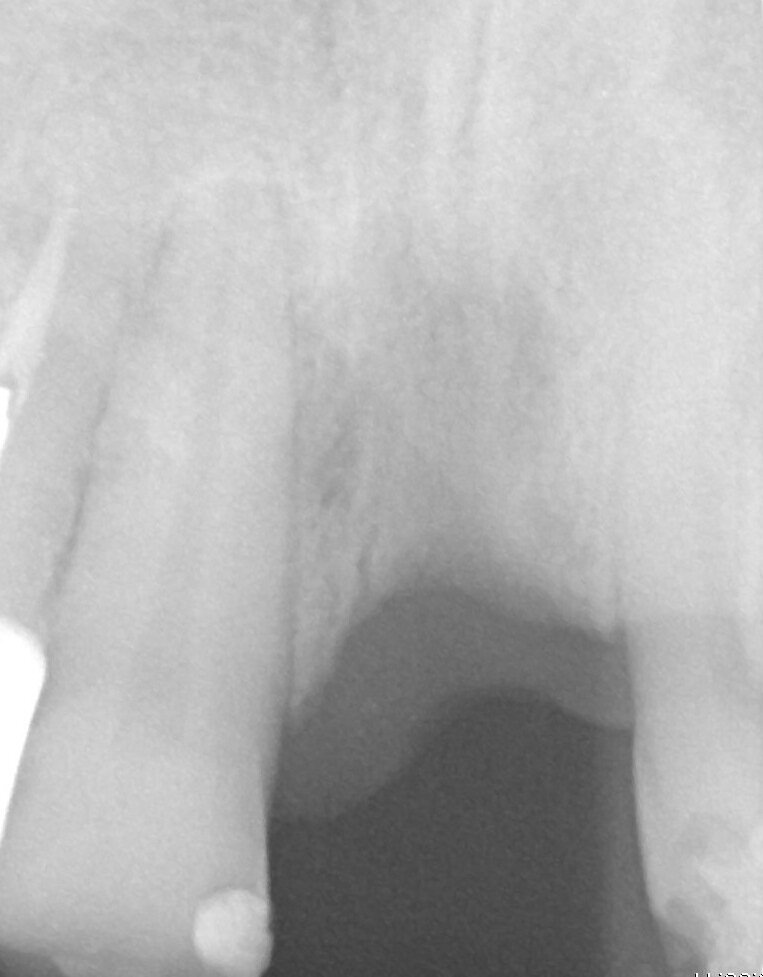

Fig. 2_Rx immediatamente dopo il posizionamento dell’impianto GTB e del Moncone Easy Slim. Notare la perfetta congruenza tra l’impianto e lo spazio di preparazione.

Paziente di sesso maschile di 60 anni di età giunto alla nostra osservazione per una edentulia parziale dovuta all’assenza dell’elemento 1,1. La situazione clinica è resa esteticamente e funzionalmente complicata dalla assenza dell’elemento 2,2 che considerato lo spostamento dei denti contigui comporta un aumentato spazio per la sostituzione protesica dell’elemento 1.1. Si effettua dopo rx di controllo il posizionamento di un impianto osteintegrato GTB diametro 3,6 x 9 mm ,con posizionamento, come da protocollo, 1,5 mm sottocrestale ed inserzione immediata di moncone easy abutment slim 3,4 x 7 mm altezza gengivale 3,5 mm. angolato a 10 gradi (Easy Abutment Slim – GTB Plan1Health Amaro, UD, Italy). Con l’ausilio di una cappetta easy si costruisce e si cementa, con tecnica extraorale, una corona provvisoria in resina acrilica con forma a pontic su elemento 1.1 in modo da eseguire un carico immediato e fornire al paziente una estetica immediata (Figg. 1-3). Dopo 12 settimane ad avvenuta osteointegrazione si provvede all’impronta definitiva eseguita a livello abutment con elastomero di precisione Aquasyl Monophase (Dentsply) e con idonea cappetta easy (GTB Plan1Health Amaro, UD, Italy). La stessa cappetta easy viene utilizzata dal laboratorio odontotecnico come cappetta da sovrafusione garantendo standard di precisione stabiliti industrialmente (Figg. 4-8). La corona costruita in lega preziosa e porcellana viene cementata dopo una settimana, fatte le prove estetiche e occlusali necessarie sul paziente. I controlli a distanza di 4 anni, sia radiografici che clinici, confermano la stabilità dell’osso intorno all’impianto e la mancanza di perdita di tessuto gengivale attorno allo stesso (Figg. 9-11).